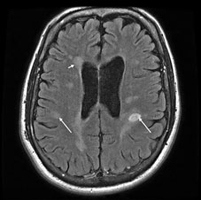

Even the most effective diagnostic tool, the MRI, can be misleading. “Sometimes the diagnosis gets made because of some white spots on the MRI scan in a person who doesn't have MS,” said Dr. Rudick. “It's not uncommon to see somebody who has fatigue or tingling and who has nonspecific spots on the MRI scan who has been told they have MS and they probably don't.” Migraines, for example, can also be associated with abnormal MRI spots.

The MRI is still a requirement for diagnosis and a good place for internists to start, the experts said. “It would certainly be best if they would refer the patient to a neurologist after having obtained a basic screening bloodwork panel and MRI scan,” said Maria K. Houtchens, MD, a neurologist at the Partners MS Center in Boston.

Then the case should be passed along or at least shared with someone who has extensive knowledge of the disease. “The MRI has to be interpreted by somebody who's an expert,” said Dr. Galetta.